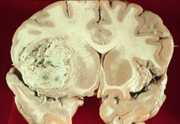

29

E. Bitemporal hemianopsia and Cushingoid features.